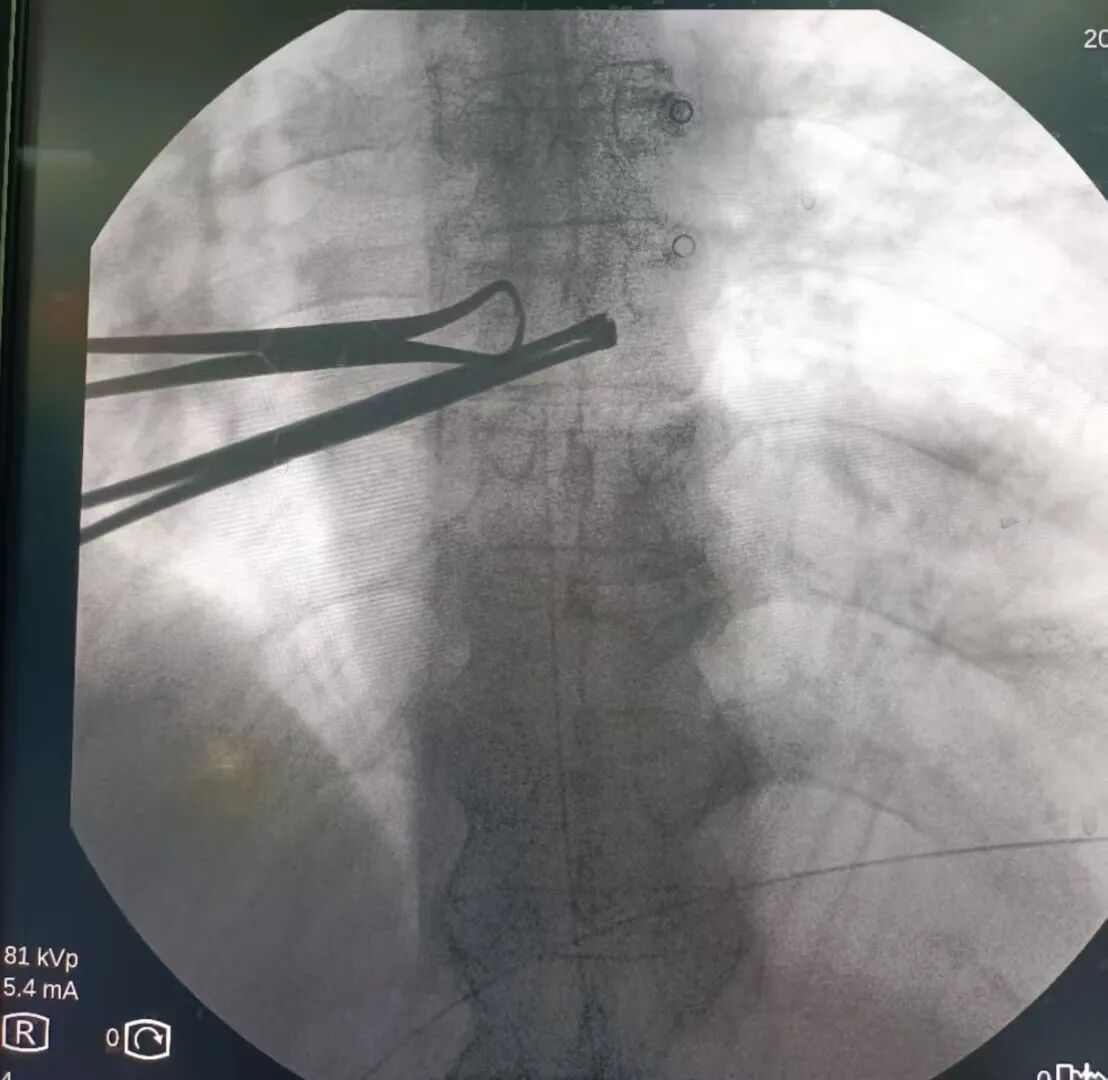

鞘内吗啡镇痛泵植入术

鞘内吗啡镇痛泵植入术,又称“植入式鞘内药物输注系统”,是一种先进的微创介入镇痛技术。它通过将药物直接输送到脊髓周围的脑脊液中,像建立一个“直达疼痛中枢的精准给药通道”,从而高效地控制顽固性疼痛。它真正实现了 “用最小的药量,达到最强的效果,产生最少的副作用”的精准医疗目标,为众多深受顽固性疼痛折磨的患者提供了重返高质量生活的希望,是“舒适化医疗”理念的杰出体现。是目前国际上治疗顽固性疼痛及癌痛的核心技术。

鞘内吗啡本治疗示意图 鞘内吗啡泵相比传统给药方式剂量对比